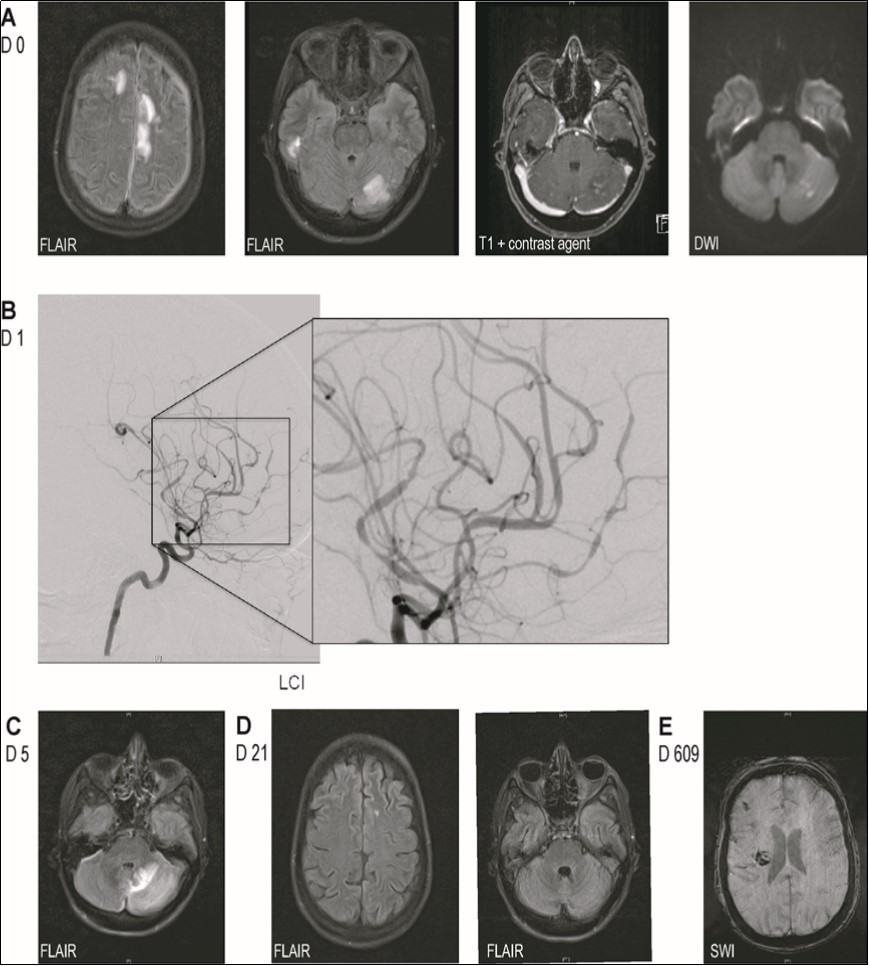

Cerebral MRI revealed multiple supra- and infratentorial FLAIR-hyperintense lesions involving both cortex and white matter. A cerebellar lesion was partially hyperintense on DWI, though without concomitant hypointensity on ADC, and showed weak contrast enhancement (Figure 1A). MR- and digital subtraction angiography displayed segmental narrowing and dilation of proximal as well as distal vessels in all territories (Figure 1C). Analysis of CSF showed normal cell count (3 cells/µl) while cytological examination revealed presence of activated lymphocytes. Glucose and lactic acid levels were normal, protein level was elevated (168mg/dl) and there was intrathecal IgM- and IgG-synthesis. Infectious causes were ruled out (including panbacterial and panfungal PCR, QuantiFERON-TB Gold in Tube Test©, CMV, EBV, enterovirus, HIV, FSME, VZV, hepatitis B/C, cryptococcus neoformans, candida and aspergillus species, borrelia burgdorferi, treponema pallidum). We diagnosed cerebral vasculitis and due to the patient's rapid decline directly administered a methylprednisolone pulse followed by an oral tapering with prednisolone without performing a biopsy. Four days after the start of steroid-therapy basal ganglia hemorrhage caused left-sided hemiplegia and anarthria. By that time, MRI showed progression of the aforementioned FLAIR-hyperintense lesions (Figure 1C) without any contrast enhancement along with new cerebellar microbleeds and bilateral narrow subdural hygroma (after lumbar puncture). On MRA intracranial artery changes had resolved. We intensified immunosuppression by administration of cyclophosphamide.

Figure 1.Imaging findings. (A) MRI-images on admission showing multiple supra- and infratentorial FLAIR-hyperintense lesions involving both cortex and white matter and one cerebellar lesion with weak contrast enhancement and partial DWI-hyperintensity. (B) Digital subtraction angiography showing segmental narrowing and dilation of proximal as well as distal vessels in all territories. (C) MRI-images 4 days after start of steroid-therapy showing progression of the FLAIR-hyperintense lesion. (D) MRI images after administration of methylprednisolone and cyclophosphamide showing nearly full regression of parenchymal lesions. (E) MRI shortly before the patient's death showing blood degradation products in the right frontal subarachnoid space and right basal ganglia.

Owing to the uncommon clinical presentation of cerebral vasculitis we screened for antineuronal-autoantibodies. Anti-DPPX-antibodies were detected in CSF and serum (both 1:100, cell-based indirect immunofluorescence assay) establishing the additional diagnosis of anti-DPPX-encephalitis. Whole body FDG-PET/CT did not suggest underlying malignancy. After cyclophosphamide and plasmapheresis the FLAIR-hyperintense lesions on MRI disappeared almost completely and MRA still showed normalization of intracranial arteries (Figure 1D). Anti-DPPX-titer dropped to 1:32. Hyperekplexia and myoclonus decreased under symptomatic treatment with clonazepame. Therapy with rituximab was started. After two months she was transferred to a rehabilitation unit from where she returned three weeks later somnolent, tetraplegic and anarthric. EEG revealed non-convulsive status epilepticus that was successfully terminated by valproate, also leading to some clinical improvement. However, as anti-DPPX-titer had risen to 1:1000 we initiated a second plasmapheresis-cycle. Thereafter anti-DPPX-titer dropped to 1:100. Another cycle of rituximab and treatment with azathioprine were started. Five weeks later she was again transferred to the rehabilitation unit, where she improved markedly, being able to use a wheelchair independently, walk over short distances in a gait training device, use her right arm and ingest food orally.

21 months after initial contact, the patient was admitted to our hospital's internal medicine unit because of an acute renal failure with urosepsis requiring hemodialysis. In addition cardiac cirrhosis with ascites was diagnosed. In the neurological examination the patient was somnolent, showed a spastic, left-sided hemiparesis and a newly increase of myclonus. Cerebral MRI displayed blood degradation products in the right frontal subarachnoid space, a new microbleed in the left temporal white matter as well as whole brain atrophy (Figure 1E). Anti-DPPX-titer had risen to 1:32000. In the further course, the patient developed aspiration pneumonia eventually causing septic shock with multiple organ failure that lead to her death at the age of 34. An autopsy was not performed (Figure 2).